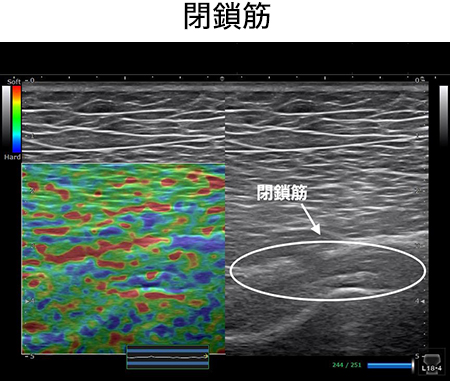

このセッションでは、血管・靭帯・神経をあなたの臨床に取り入れやすくするために筋膜との関係性を明らかにします。例えば腕神経叢は斜角筋と繋がりがありますし、坐骨神経は梨状筋との繋がりがあります。この知識さえあれば、どのタイミングで血管や神経を見ればいいのかがわかり。明日からの臨床ですぐに結果を出すことができるでしょう。

なぜ、僕たちがこんなにも疼痛治療の最前線で、結果を出し続けているのか?それは、正確な触診技術にあります。このセッションでは、ほとんどの理学療法士が知らず、学校では決して教えない、僕たちが日々の研究で獲得した、エコー解剖学に基づいた血管・靭帯・神経を確実に触診するための3つのポイントをお伝えします。